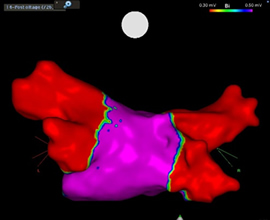

三次元マッピングを用いた高周波アブレーション

高周波カテーテルアブレーションはカテーテル先端より高周波電流を流して熱を発生させて焼灼する方法です。発作性~持続性心房細動、心房粗動、発作性上室性頻拍、心室頻拍など幅広く不整脈を治療することが可能です。三次元マッピングを使用することにより、正確な手技、手技時間の短縮、放射線被爆の軽減、合併症の予防が可能です。